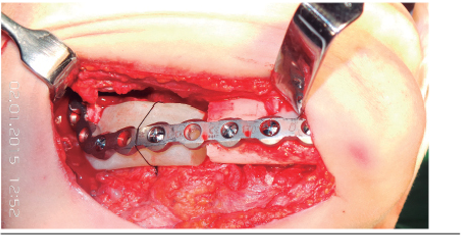

En el caso descrito se indicó la resección en bloque de la lesión con márgenes de seguridad mediante un acceso quirúrgico extraoral. Para la planificación se utilizó un modelo estereolitográfico, el cual sirvió para la adaptación de una placa de reconstrucción y para la confección de un bloque de acrílico con la forma del segmento mandibular a resecar. Éste fue fabricado mediante la toma de impresión con alginato en la estereolitografía, realizándose posteriormente un vaciado con cera rosada para obtener como resultado final el bloque acrílico de termocurado, el cual incluyó en su mezcla gentamicina al 1%.

Durante el intraoperatorio el bloque es fijado a la placa de reconstrucción utilizando tornillos de osteosíntesis (Figura 4), con el fin de dar sostén a los tejidos blandos, conservando un contorno anatómico adecuado y manteniendo el espacio para la colocación posterior del injerto óseo.